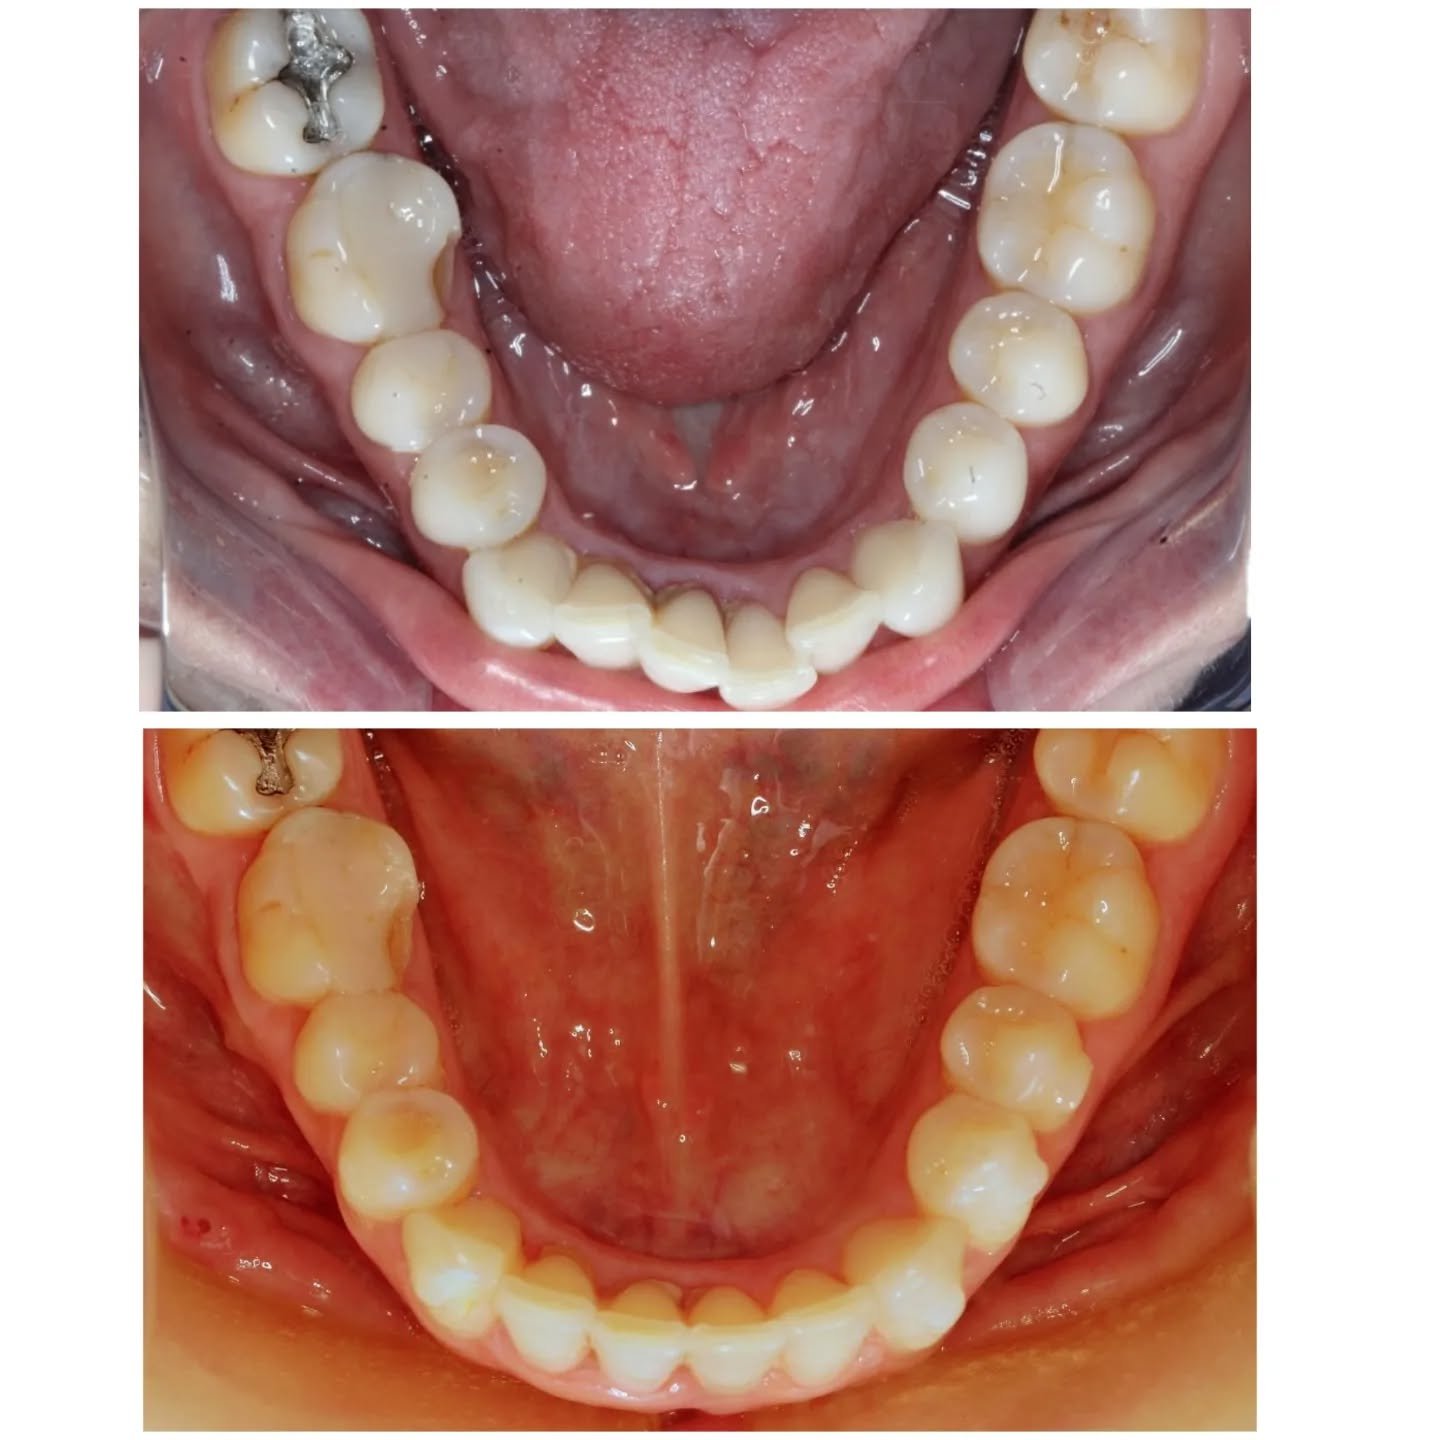

Resultados Reais

Veja como o invisalign transformou o sorriso dos nossos pacientes